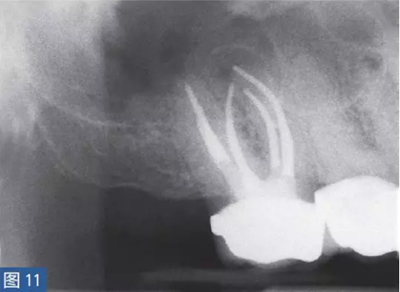

慢性根尖周膿腫(圖10 和11)是由長(zhǎng)期持續(xù)的炎癥引起的。膿液穿通骨和口腔黏膜,并通過(guò)口腔黏膜或上皮的瘺管流出。這些通到表皮的瘺管通??赡茏鳛槠つw損傷而被錯(cuò)誤處置。此外,瘺管也可能存在于牙周并通過(guò)齦溝引流。瘺管可以部分或完全地被上皮所包繞,這些上皮又被炎性結(jié)締組織包圍。

臨床診斷顯示牙髓電活力測(cè)試結(jié)果為陰性。除非瘺管閉合,否則叩診和觸診通常都不會(huì)引起疼痛。放射學(xué)檢查,根尖周組織表現(xiàn)從無(wú)變化到發(fā)生明顯變化。

圖10:17 牙齒CAA。術(shù)前放射學(xué)檢查,利用牙膠尖顯示瘺管。患者因17 牙齒局部瘺管而前來(lái)就診,訴無(wú)特殊臨床癥狀。

圖11: 17 牙齒CAA。根管治療12 個(gè)月后。